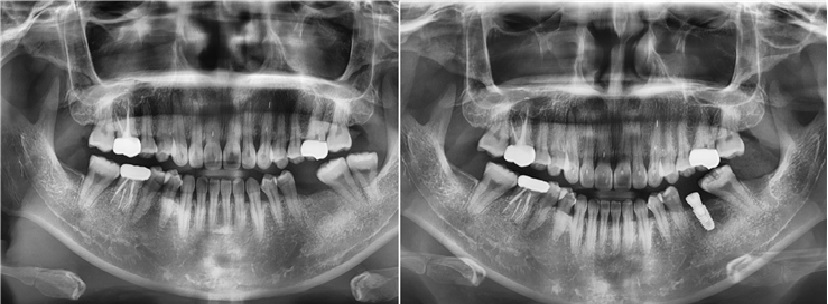

치료전후사진